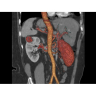

• Неинвазивная оценка состояния коронарных артерий.

• Диагностика атеросклероза и других сердечно-сосудистых патологий.